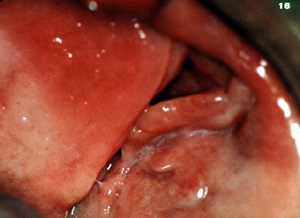

| El épulis

fisurado representa una masa hiperplásica de la mucosa, generalmente en

el vestíbulo de la boca, proliferando como una reacción a la

irritación mecánica de largo

plazo de una prótesis dental mucosoportada mal adaptada.

Aquí son

dos épulis, bilaterales, en los vestíbulos del maxilar. Es una

apariencia típica. Son lobulados y

muestran áreas focales aumentadas de vascularidad. En la porción

central de cada masa hay una ranura ó una invaginación

que corre en una dirección anterior-posterior. La pestaña de la

dentadura postiza encajará en estas ranuras.

| Esta vista más

aumentada de la lesión del lado izquierdo

está compuesta de por lo menos tres pliegues de tejido bastante

denso. Hay invaginaciones profundas entre los pliegues.